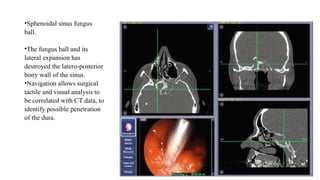

•Sphenoidal sinus fungus

ball.

•The fungus ball and its

lateral expansion has

destroyed the latero-posterior

bony wall of the sinus.

•Navigation allows surgical

tactile and visual analysis to

be correlated with CT data, to

identify possible penetration

of the dura.